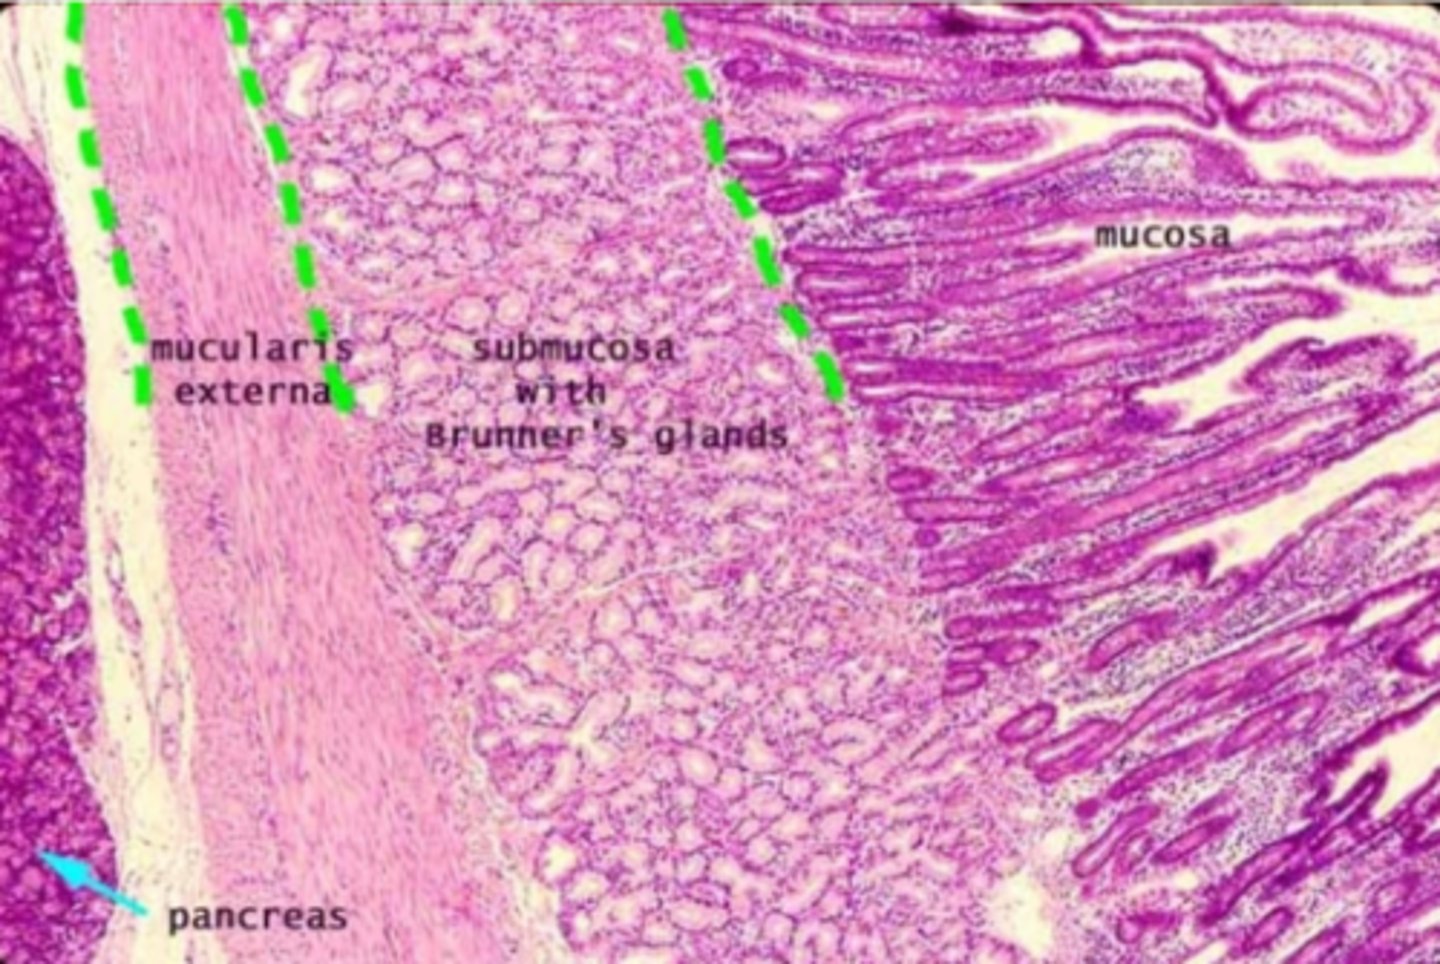

duodenum

What is this?

Brunner's glands

What are the glands in the duodenum?